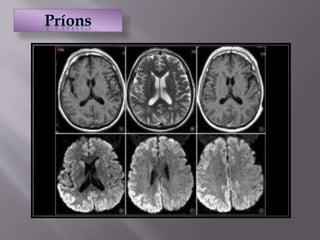

 Organismo infeccioso formado por proteínas

 Possui a capacidade de se autoduplicar

 Não possuem DNA ou RNA  diferença com vírus e

bactérias

 Causa Encefalopatia espongiforme: morte de neurônios e

amolecimento do cérebro

 Não possui cura  sempre fatal

 São extremamente resistentes: calor, radiação UV,

remédios, enzimas...

 E nosso sistema imune é incapaz de matá-lo

 Organismo infecciosoformado por proteínas  Possui a capacidade de se autoduplicar  Não possuem DNA ou RNA  diferença com vírus e bactérias  Causa Encefalopatia espongiforme: morte de neurônios e amolecimento do cérebro  Não possui cura  sempre fatal

 São extremamenteresistentes: calor, radiação UV, remédios, enzimas...  E nosso sistema imune é incapaz de matá-lo  A infecção pode ocorrer por: 1. herança genética 2. Consumo da carne de animais infectados 3. Aplicação de hormônios 4. Utilização de instrumentos cirúrgicos contaminados